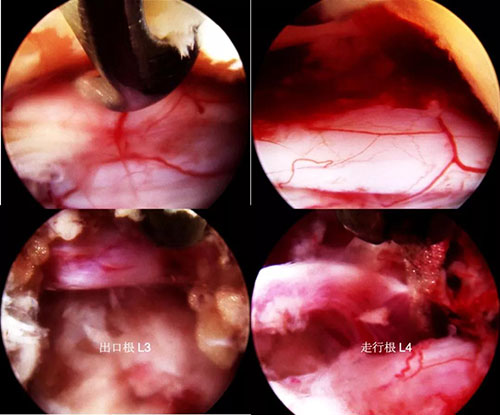

处理黄韧带,显露神经

置入工作通道,撑开,试模,置入椎间融合器